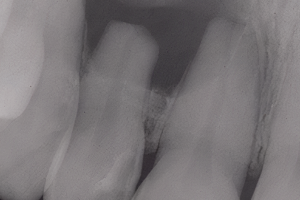

Трудности в лечении этого зуба связаны с тем, что его мезиодистальная ширина намного меньше (Рис. 1А) по сравнению с вестибулярно-язычной шириной (Рис. 1В), что делает очень трудным, если не невозможным, расширение канала или каналов полностью в любом направлении.

Рисунок 1. A. Нижний центральный резец. Обратите внимание на малую мезиодистальную ширину корня. B. Корень того же зуба значительно шире в вестибулярно-язычном направлении. Обратите также внимание на вогнутость на уровне средней трети.